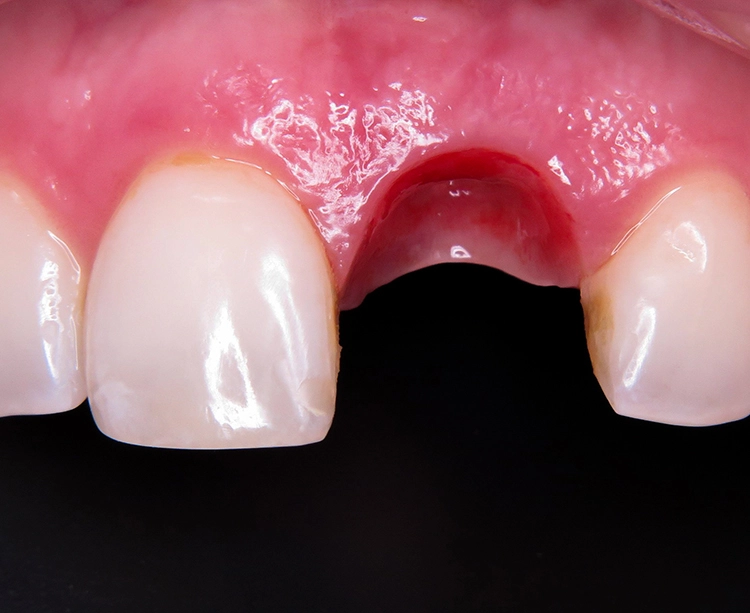

Theoretisch wäre die digitale Datenerfassung mit dem Intraoralscanner möglich, allerdings sind die Scanpfosten nicht radioopak, so dass eine exakte radiologische Kontrolle nicht möglich ist. Im Dentallabor wurde zunächst das vollkeramische Abutment gefertigt und nach dessen Einprobe die vollkeramische Krone hergestellt (Abb. 28 bis 30). Nach dem Verschrauben der Krone im Mund konnte der Schraubenkanal mit Komposit verschlossen werden. Es zeigt sich eine stabile Situation mit einem gesunden peri implantären Weichgewebe und harmonischem Gingivaverlauf (Abb. 31a und b).